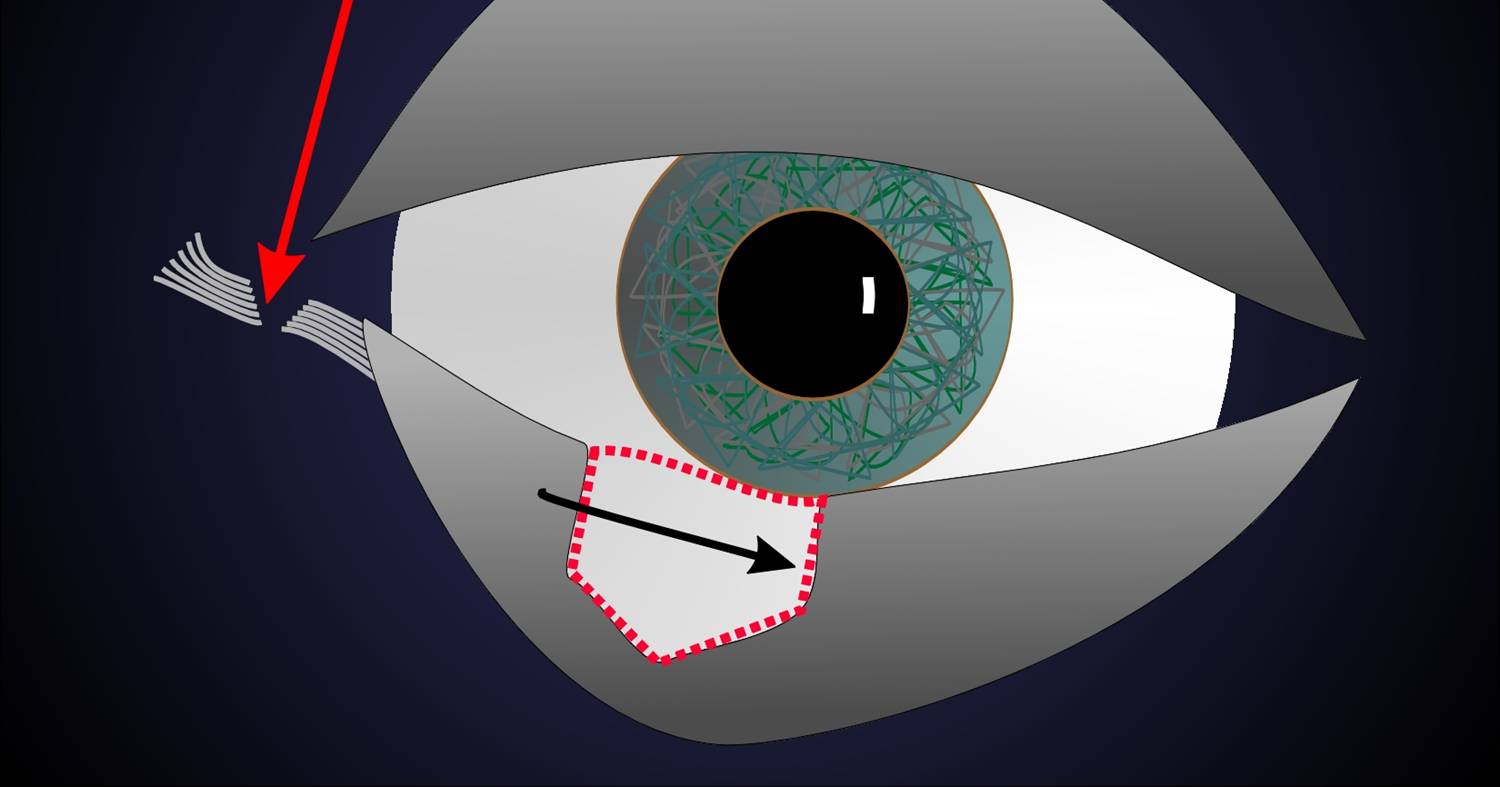

Fig. 2: Para defectos mayores de un tercio podemos facilitar la transposición (flecha negra) del resto lateral del párpado si cortamos el ligamento lateral del párpado (cantolísis, flecha roja). |

Las incisiones, necesarias en el margen palpebral para eliminar el tumor, tienen que efectuarse en el mismo ángulo para poder reunir los restos del párpado y formar una línea recta del nuevo margen. Los defectos de hasta un tercio se pueden cerrar por transposición de los dos tercios restantes del párpado. Los defectos algo más grandes se pueden cerrar si hay bastante laxitud o si se desconecta el resto del párpado lateral del margen orbitario, esto se consigue con una sección del tendón palpebral lateral en el ángulo lateral (cantolísis lateral).